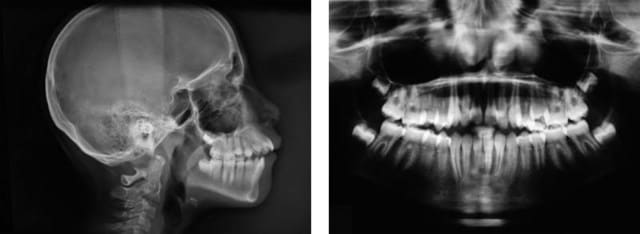

redevenons sérieux!!!

ce cas t'intéresse dam dam?

@+ Bjc.

2 sje922 - Eugenol

1 uql4tq - Eugenol